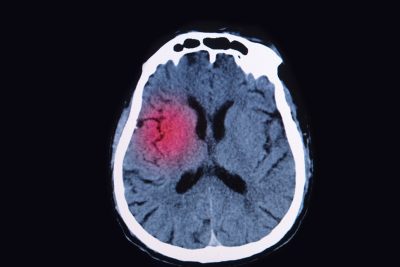

Some ethics consultations involve brain-injured patients who are unresponsive, and contain discussions center around withdrawing life-sustaining interventions. At least for some of those patients, there may be more hope for recovery than previously was believed to be the case, a recent study suggests. A surprising number of patients with brain injury who are unresponsive to behavioral commands can perform cognitive tasks that can be detected with neurotechnology, researchers found.1 For 241 patients with disorders of consciousness, researchers assessed volitional response to commands on functional magnetic resonance imaging or electroencephalography. The researchers detected cognitive motor dissociation in 25% of participants without an observable response to verbal commands.

First, the study was investigational. It’s not ready for clinical dissemination yet, because we have to better understand the test characteristics. It, however, does show that a prevalence of 25% of patients, who were thought to be in a coma or a vegetative state, may have the ability to respond to volitional commands. It’s not a passive response. We asked people to imagine playing tennis or walking through their house, and you have to hold that in memory and then execute the task. We think that the presence of cognitive motor dissociation may actually be higher, because it’s harder to follow those commands than just be covertly conscious.

This study shows that there is heterogeneity in brain states that appear the same at the bedside. Under the hood, patients are different than they appear to be. And that difference really makes a difference as far as prognosis — and, perhaps, in responsiveness to therapeutics.